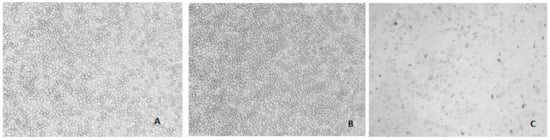

2.3. Effect on Human Leydig Cells (In Vitro)

4.6.1. Cell Lines

4.6.2. MTT Viability Assay